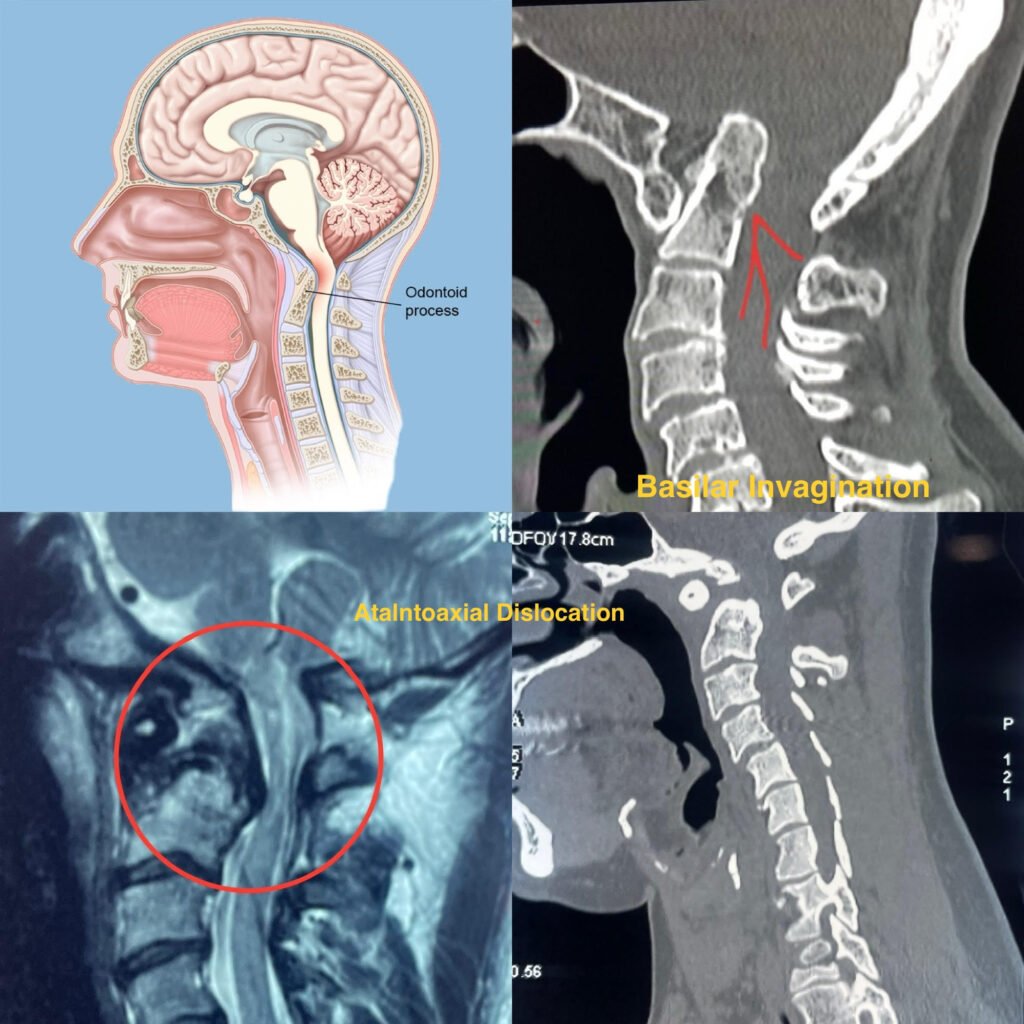

Craniovertebral Junction Anomalies

What is CRANIOVERTRABLE JUNCTION ANOMALIES

Craniovertebral Junction Anomalies are abnormalities that affect the connection between the base of the skull (cranium) and the upper part of the spine (vertebrae). These anomalies can involve malformations of the bones, ligaments, or other structures in this region.

• Diagnosis typically involves a combination of medical history, physical examination, and imaging studies such as X-rays, CT scans, or MRI.